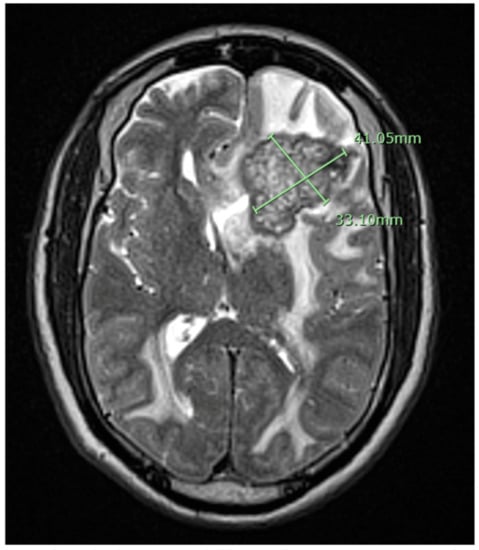

2. Case Presentation